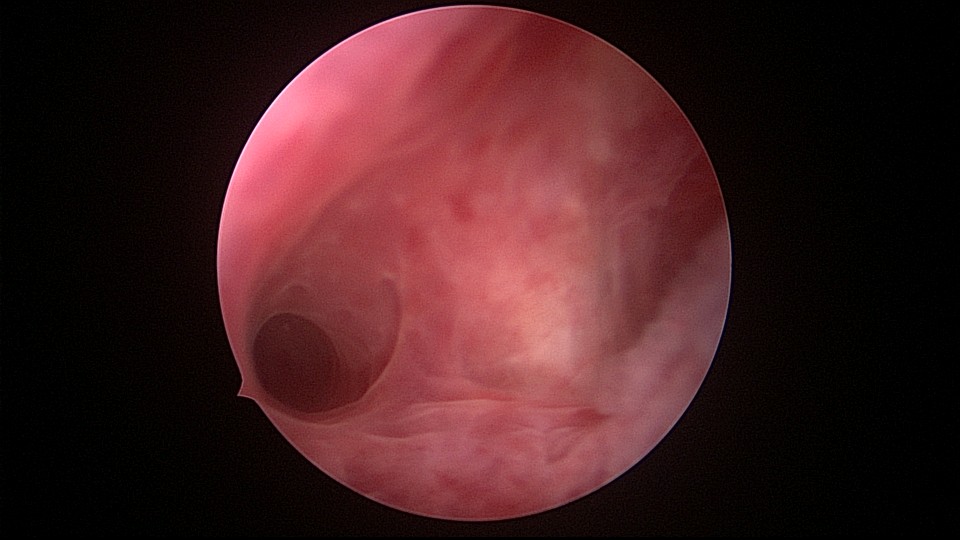

患者34岁,G4P1,顺产1次,继发不孕,宫腔容积小,宫腔粘连。2020年9月宫腔镜探查,见宫腔下段幕状粘连,两侧小孔与宫腔上段相通,形成假的输卵管开口。双极电针切开粘连,宫腔形态恢复正常,显露双侧输卵管正常开口。2020年10月宫腔镜二探取球囊,宫腔形态正常,双侧输卵管开口可见。2021年6月自然妊娠,2022年2月足月剖宫产分娩,2023年5月再次妊娠1次,人流终止妊娠。现39岁,G6P2,顺产1次,剖宫产1次。